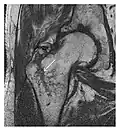

Figure 1: A 56-year-old woman presenting with left knee pain after a fall. (a) Initial anteroposterior radiograph was considered normal, however, subtle cortical disruption of the anterior rim of the medial tibial plateau, medial to the tibial spine, is noted (arrow). (b) Coronal T1-weighted MRI confirms the cortical disruption (arrow) and shows extensive fracture through the proximal tibia. (c) Coronal proton density-weighted image with fat saturation shows extensive edema in the subchondral bone. Note also hypersignal adjacent to the medial collateral ligament corresponding to a grade I sprain (arrowheads).[1]